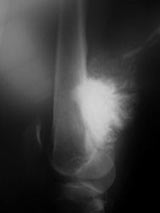

X-Rays:

- Lobulated and ossified exophytic mass (cauliflower-like) adjacent to the cortex; attached to metaphyseal cortex via a broad base

- Centrally, the tumor is radiodense (demonstrates ossification)

- Peripherally there may be small radiolucies that represent low grade cartilaginous lobules, fibrous tissue or fat

- The underlying cortex may be thickened

- There is no periosteal reaction since the tumor comes from the outer layer of the periosteum and therefore does not elevate the periosteum.

- Large tumors encircle the bone

- Appears to have broad attachment to underlying cortex with a cleft between exophytic base and cortex at periphery. This is referred to as a “String Sign” (cleft is often only identifiable on CT scan)

- There may be invasion of the medullary canal with long standing disease

- High grade or defifferentiated areas may appear as large radiolucent areas/mass adjacent to radiodense areas